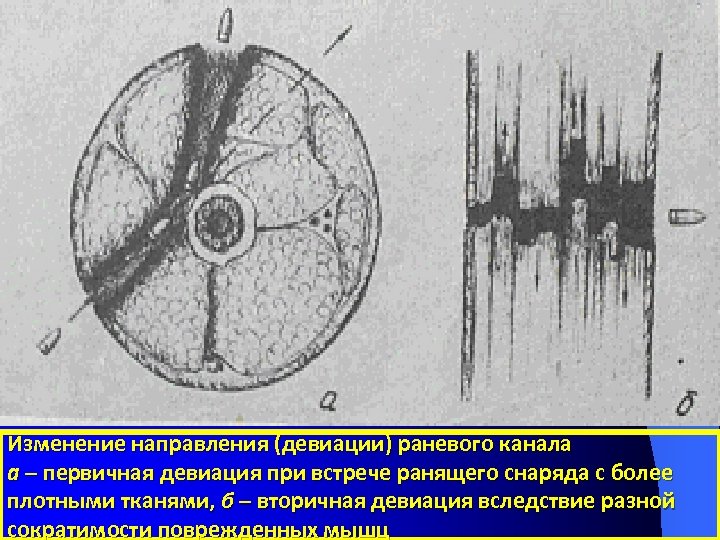

Изменение направления (девиации) раневого канала а – первичная девиация при встрече ранящего снаряда с более плотными тканями, б – вторичная девиация вследствие разной сократимости поврежденных мышц

Изменение направления (девиации) раневого канала а – первичная девиация при встрече ранящего снаряда с более плотными тканями, б – вторичная девиация вследствие разной сократимости поврежденных мышц